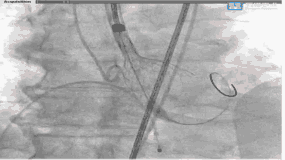

瓣膜释放,彰显配合精准

瓣膜释放后形态位置良好,造影微量返流